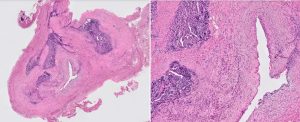

A female patient in her 40s presented with renal impairment. CT intravenous pyelography demonstrated longstanding right hydronephrosis and hydroureter with lower ureteric obstruction. At ureteroscopy there was a lesion in the right lower ureter that was biopsied (three biopsies, each 1mm). This was followed by right distal ureterectomy and ureteric reimplantation. The first four images are from the diagnostic biopsy and the last image is from the resection specimen.

The distal ureterectomy specimen showed endometriosis with similar features to the initial ureteric bioipsy that infiltrated the ureteric muscularis propria and formed a mass undermining unremarkable urothelium. There was no evidience of hyperplasia, atypia or malignancy.

Endometriosis is defined by the implantation of stroma and/or endometrial glandular epithelium outside the uterus [1]. While it can affect various anatomical sites, urinary tract involvement occurs in approximately 1% of all patients with endometriosis [2]. Of patients with urinary tract endometriosis, the most frequently affected site is the bladder (84%), followed by the ureters (10%), kidney (4%) and urethra (2%) [3]. Ureteric endometriosis can present with flank pain, dysuria, gross haematuria, uraemia and pelvic mass. However, approximately 50% of patients are asymptomatic with high degree of obstruction over a long time leading to deterioration in renal function. There are two ureteric endometriosis types: intrinsic and extrinsic. The latter occurs four times more frequently and endometriotic lesions invade only the outer layer of the ureter and in some cases may lead to ureteric obstruction. In intrinsic endometriosis, endometriotic lesions invade the muscularis propria, and even the ureteric lumen, as in this case. Ureteric endometriosis can mimic other pathologies, most importantly malignancy, and ureteroscopy with biopsy is the most precise diagnostic option [4].